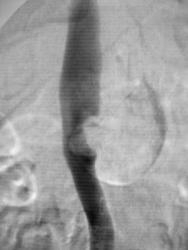

A renal artery aneurysm (RAA) is defined as a dilated segment of renal artery that exceeds twice the diameter of a normal renal artery. Symptomatic RAAs can cause hypertension, pain, hematuria, and renal infarction.